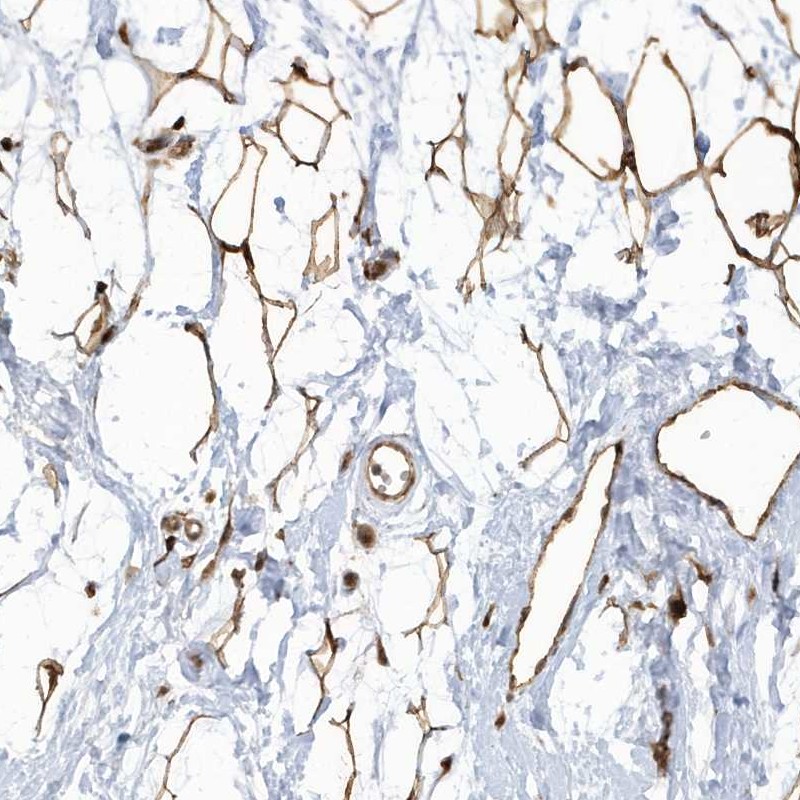

Immunohistochemical staining of human breast shows strong cytoplasmic positivity in adipocytes.